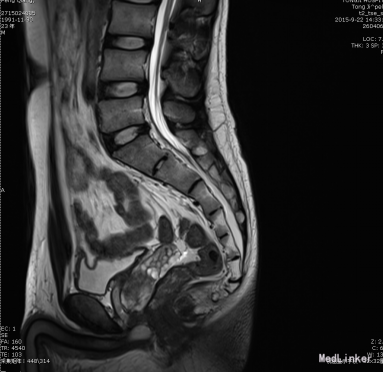

患者,男,23岁。 主诉:进行性排尿困难4年余。 现病史:患者4年前无明显诱因出现排尿困难,夜尿1次,间或有排尿不尽感。于当地医院抗感染治疗,症状未见明显好转。2015-9-21于我院行尿动力检查示:膀胱初感觉减退;膀胱收缩力弱+;残余尿134ml。2015-9-22于我院行腰骶丛MRI示:双侧S1、S2神经根处束膜囊肿,最大位于右侧S2神经根处,大小5*6mm。 既往史:既往体健,未诉异常。

查体:T: 36.5 ℃ P:64 次/分 R: 20 次/分 BP: 108/73 mmHg;双肾区无叩痛,输尿管走行区压痛(-),脊柱四肢活动正常,肛门外生殖器无异常。 辅助检查: 2015-9-21于我院行尿动力检查示:膀胱初感觉减退;膀胱收缩力弱+;残余尿134ml。2015-9-22于我院行腰骶丛MRI示:双侧S1、S2神经根处束膜囊肿,最大位于右侧S2神经根处,大小5*6mm。 尿液常规分析:红细胞(隐血) (±) ↑ 白细胞(粒) 2+ ↑ 红细胞计数 14.4 ↑ /ul 白细胞计数. 上皮细胞计数 18.5 ↑ /ul 495.00 ↑ /ul。